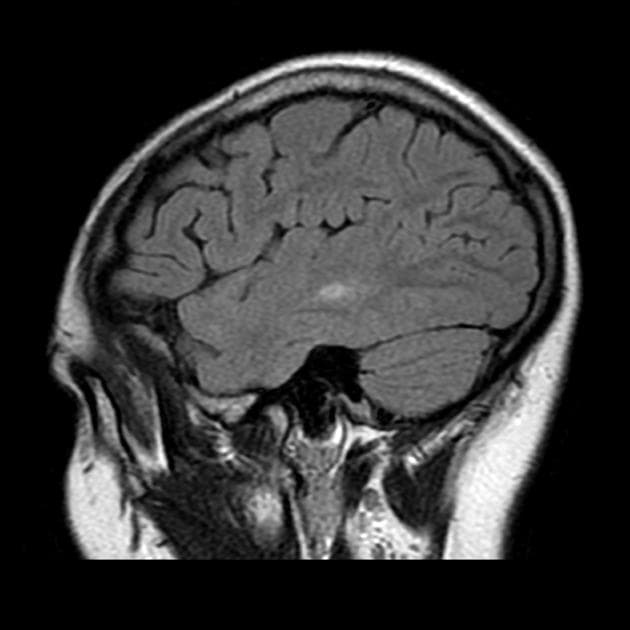

- Tăng tín hiệu trên hình ảnh T2/FLAIR kèm hạn chế khuếch tán rõ rệt, đối xứng hai bên, ảnh hưởng đến chất trắng, đặc biệt vùng trên lều (bán nguyệt phóng xạ, trung tâm bán nguyệt), cuống tiểu não giữa, và chi sau của bao trong, lan xuống đến cuống não.

- Các sợi U dưới vỏ được bảo tồn (nhận thấy rõ nhất trên FLAIR và T2).

Hình ảnh tổn thương đặc trưng bởi tính đối xứng rõ rệt, khu trú ở những vùng chất trắng cụ thể và bảo tồn các sợi U dưới vỏ (subcortical U-fibers).

Tổn thương khu trú tại cuống tiểu não giữa hai bên (bilateral middle cerebellar peduncles) gợi ý một danh sách chẩn đoán phân biệt đặc hiệu; tuy nhiên, hầu hết các nguyên nhân khác không phù hợp với bối cảnh lâm sàng này.

Trong bối cảnh hóa trị, những thay đổi hình ảnh này gần như chắc chắn biểu hiện cho bệnh lý chất trắng do độc chất (toxic leukoencephalopathy), nguyên nhân có khả năng nhất là do 5-fluorouracil.